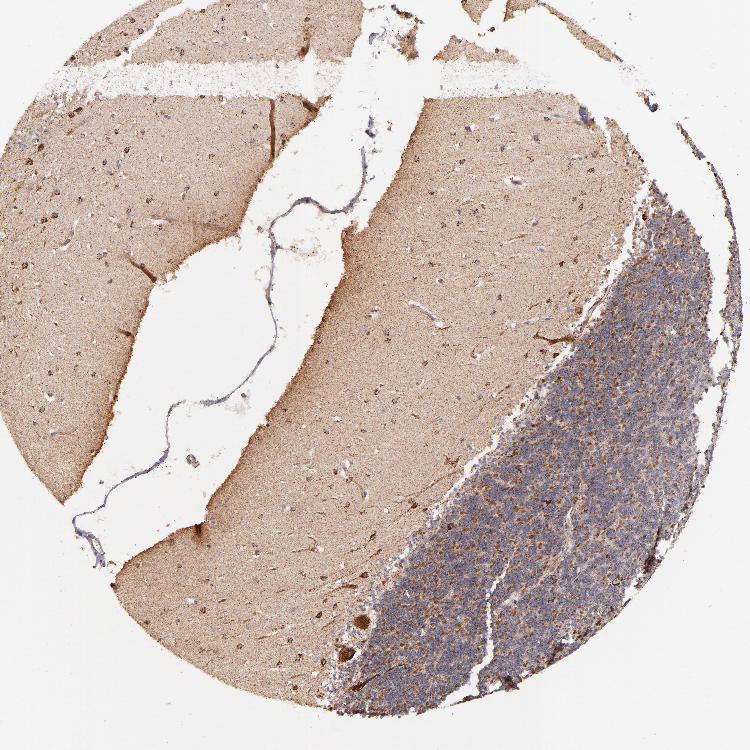

BRAIN CEREBELLUM Show tissue menu

CEREBELLUM - Expression summary

CEREBELLUM - Antibody stainingi

Antibody staining in the annotated cell types in the current human tissue is reported as not detected, low, medium, or high, based on conventional immunohistochemistry profiling in selected tissues. This score is based on the combination of the staining intensity and fraction of stained cells.

Each image is clickable and will lead to virtual microscopy that enables deeper exploration of all samples and also displays staining intensity scores, fraction scores and subcellular localization as well as patient and tissue information for each sample.

Antibody HPA000425Antibody HPA002017

Purkinje cells HighHigh

Cells in granular layer LowHigh

Cells in molecular layer MediumHigh